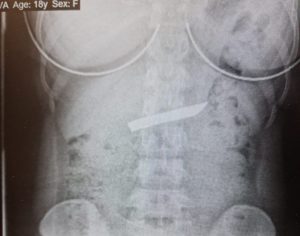

צילום רנטגן, בו ניתן לראות את להב הסכין בבטן העליונה של הנערה. צילום: המרכז הרפואי לגליל נהריה

הנערה גילתה לצוותים הרפואיים כי במהלך הארוחה בלעה להב של סכין מטבח. בצילום רנטגן שנעשה לנערה התגלה חפץ גדול בקיבה והיא הועברה למכון הגסטרו. אלא ששם לא ניתן היה להוציא את הסכין בשל גודלו ועוביו, והיה ברור כי ניתן לעשות זאת רק באמצעות הליך כירורגי.